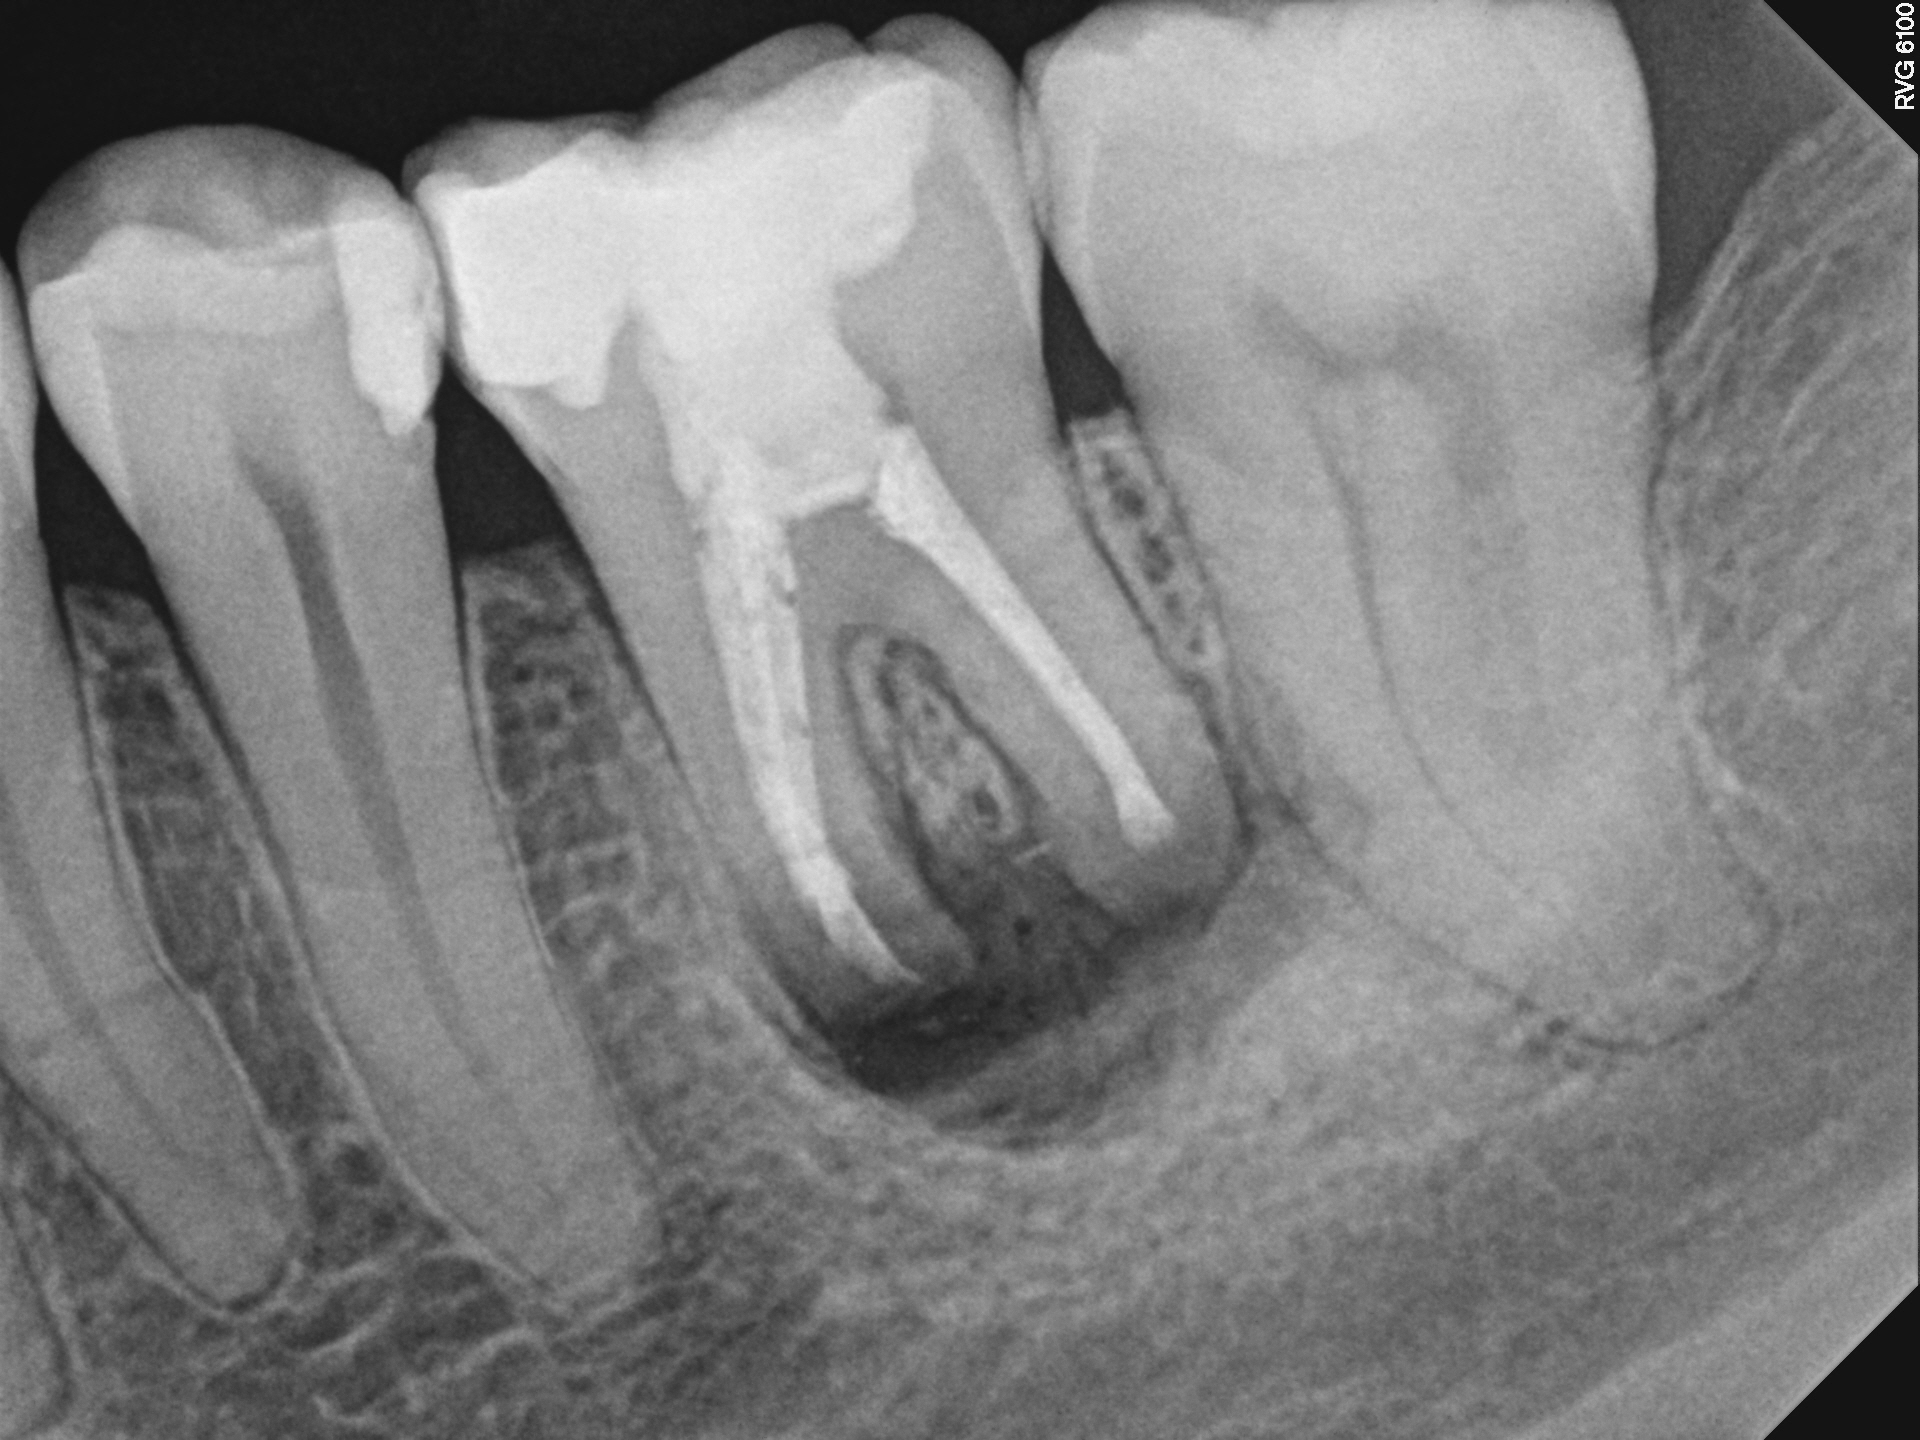

Case 2

This is a retreatment case. The picture on the left shows a lower molar that had been root canal treated many years prior, but either did not heal or at some point afterward became re-infected. The lesion is quite large, extending to the inferior alveolar nerve. While retreating the case Dr Cottle found a previously missed nerve canal (three in one root, five total in this one molar) and was able to disinfect all the canals again. The image on the right shows the completely healed bone one year later.